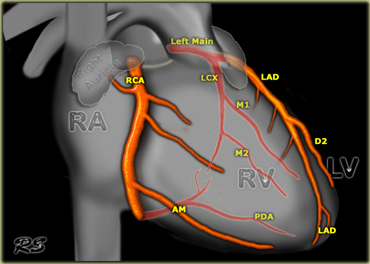

What vessel can be viewed on the anterior side of the heart

LAD

LABEL THEM

AO

PA

MITRAL

TV